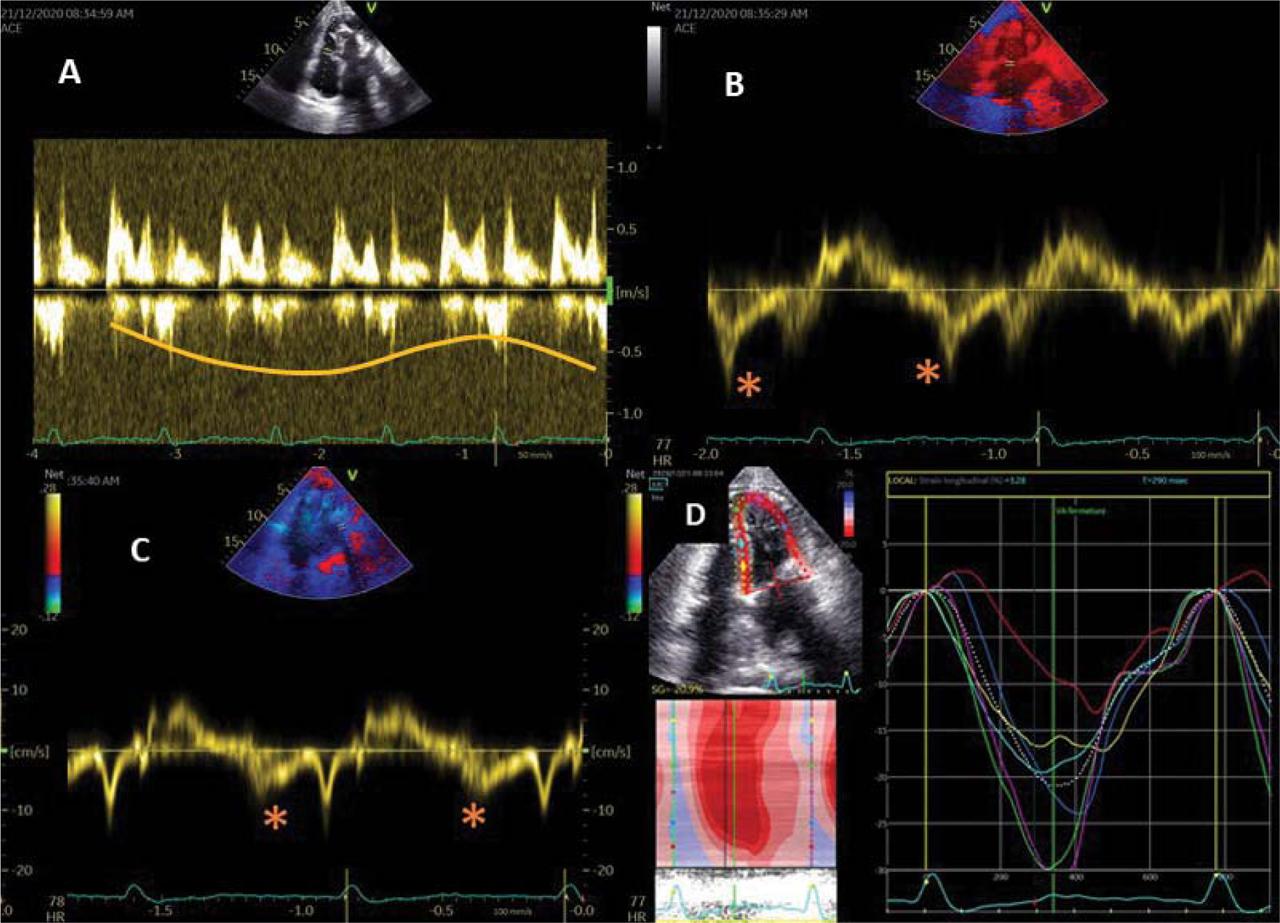

Figure 3

A) amplitude change of the mitral inflow according to the inspiration / expiration >25%. B-C) e’ septal >e’ lateral. D) delayed and weaker longitudinal deformation at the base than at the apex.